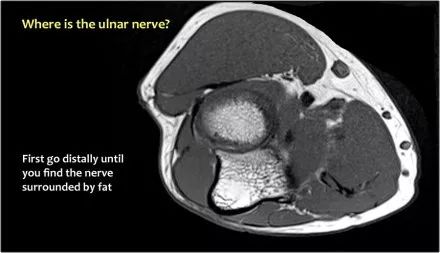

当他们将尺神经带出隧道时,他们把它放在哪里,它可以是皮下,肌肉下或肌肉内。

因此,当我们回到图像时,您会发现很难找到神经。任何这些皮下结构都可以是转位神经。一种方法是远端跟随结构,直到你发现远端的尺神经位于由脂肪包围的前臂近端的正常位置。然后当你向近端跟随它时,你会发现这是皮下移位。

在这种情况下,有神经炎。神经增大。在T2W图像上有高信号。另一个标志是在矢状图像(箭头)上看到的束的不均匀扩大。